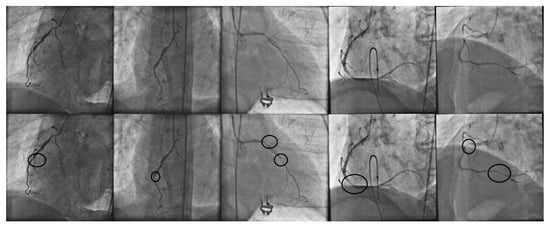

Coronary heart disease is the main cause of morbidity all over the world [1]. Consequently, it is highly important for coronary stenosis to be detected and diagnosed by cardiologists and addressed in computational science. Nowadays, X-ray coronary angiography is the main source of decision making in stenosis diagnosis. In order to detect coronary stenosis, a specialist performs an exhaustive visual examination of the entire angiogram, and based on their knowledge, the stenosis regions are labeled. In order to illustrate the challenging and laborious task carried out by the specialist in terms of the visual examination of coronary angiograms, in Figure 1, a set of X-ray angiograms along with manually detected stenosis regions is presented.

Figure 1.

(First row): set of X-ray coronary angiograms and the corresponding stenosis regions manually detected by cardiologist (second row).